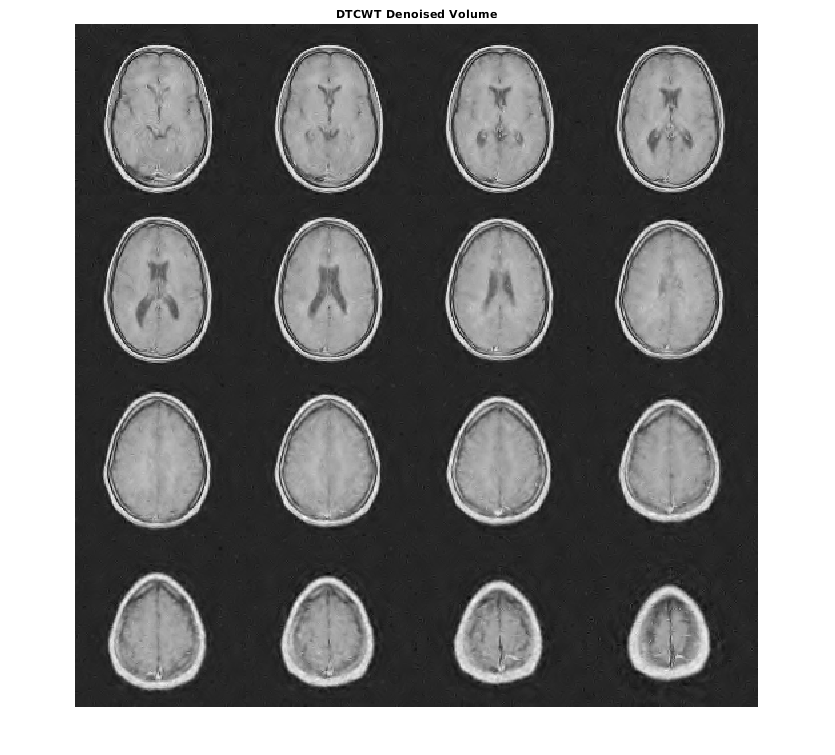

Denoise набор данных MRI вниз к уровню 4 с помощью и DTCWT и DWT. Подобные длины фильтра вейвлета используются в обоих случаях. Постройте получившийся ОСШ в зависимости от порога. Отобразите denoised результаты и для DTCWT и для DWT, полученного в лучшем ОСШ.

[imrecDTCWT,imrecDWT] = helperCompare3DDenoising(origMRI,noisyMRI);

figure montage(reshape(imrecDTCWT,[128 128 1 16]),'DisplayRange',[]) title('DTCWT Denoised Volume')